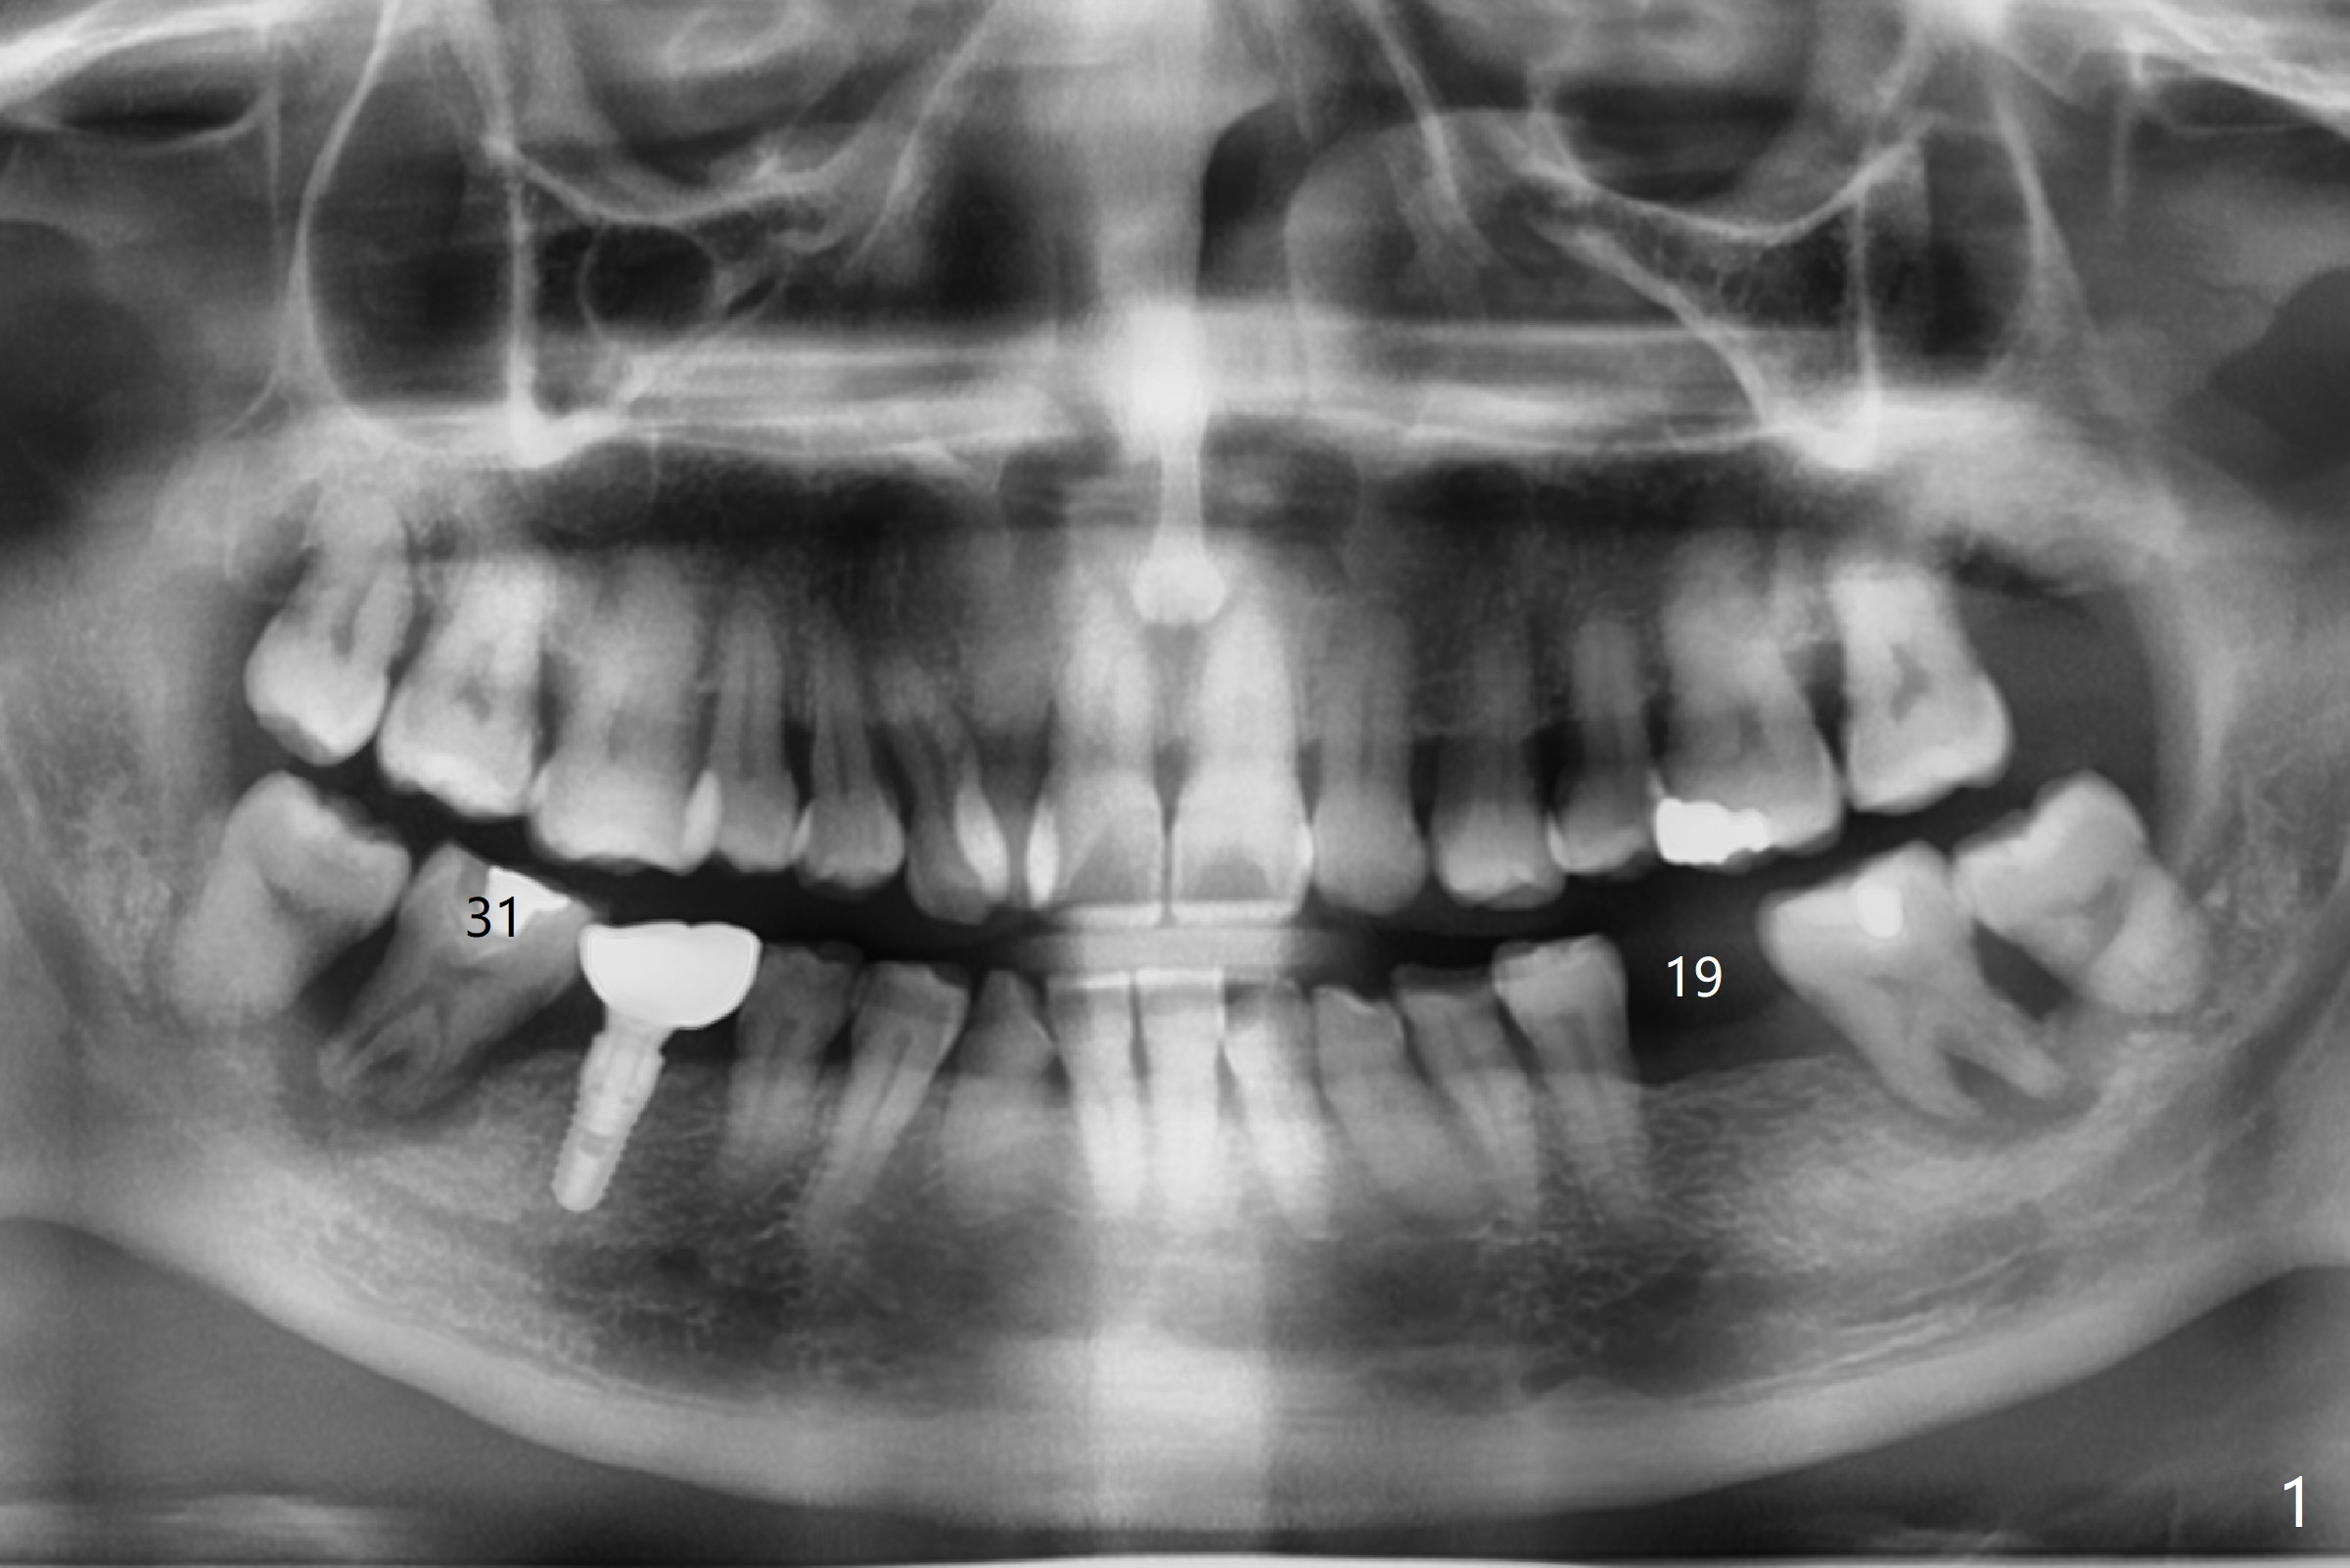

A 50-year-old man with severe chronic periodontitis and bruxism returns to clinic with chief complaint of a loose bottom right back tooth at #31 after implant placement at #19 and 30 (Fig.1,2). How to treat this case?